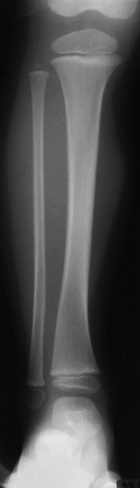

N.L. - 3 year old female with right calf mass; she denies any pain, her mother noticed it four weeks ago